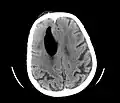

Pneumocephaly

CT scans of patients with a tension pneumocephalus typically show air that compresses the frontal lobes of the brain, which results in a tented appearance of the brain in the skull known as the Mount Fuji sign.[1][2][3] The name is derived from the resemblance of the brain to Mount Fuji in Japan, a volcano known for its symmetrical cone. In typical cases, there is a symmetrical depression near the midline (such as the crater of a volcano), due to intact bridging veins.[3] Its occurrence seems to be limited to tension pneumocephalus (not occurring in pneumocephalus without tension).[4] The sign was first described by a team of Japanese neurosurgeons.[5]